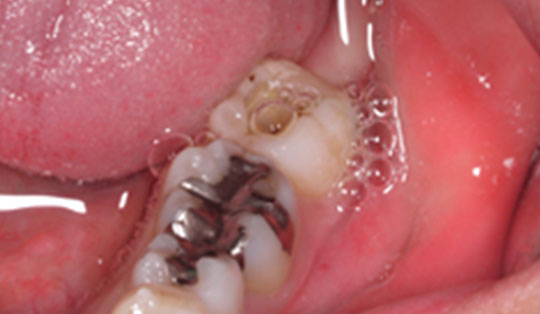

図1:以前、歯に被せたものの隙間から細菌が侵入し、根の部分で炎症が再発してしまった場合

図2:虫歯を放置し、歯の神経まで侵食してしまった場合

もっとも多いのは、むし歯が深く進行して歯髄に達した場合です。冷たいものや温かいものがしみるだけでなく、何もしていなくてもズキズキと強い痛みが続くようになったら、歯髄にまで炎症が及んでいる可能性があります。

次に、過去に治療した歯の根の先に膿がたまった場合です。以前に根管治療を受けた歯でも、時間の経過とともに再び細菌感染が起こることがあります。これを「根尖性歯周炎(こんせんせいししゅうえん)」と呼び、再治療(感染根管治療)が必要になります。